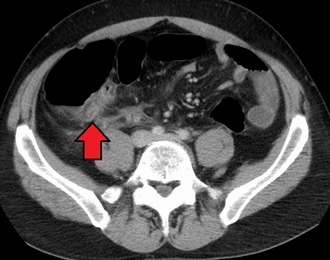

Abdominal ultrasonography, preferably with doppler sonography, is useful to detect appendicitis, especially in children. Ultrasound can show the free fluid collection in the right iliac fossa, along with a visible appendix with increased blood flow when using color Doppler, and noncompressibility of the appendix, as it is essentially walled-off abscess. Other secondary sonographic signs of acute appendicitis include the presence of echogenic mesenteric fat surrounding the appendix and the acoustic shadowing of an appendicolith.[55] In some cases (approximately 5%),[56] ultrasonography of the iliac fossa does not reveal any abnormalities despite the presence of appendicitis. This false-negative finding is especially true of early appendicitis before the appendix has become significantly distended. Also, false-negative findings are more common in adults where larger amounts of fat and bowel gas make visualizing the appendix technically difficult. Despite these limitations, sonographic imaging with experienced hands can often distinguish between appendicitis and other diseases with similar symptoms. Some of these conditions include inflammation of lymph nodes near the appendix or pain originating from other pelvic organs such as the ovaries or Fallopian tubes. Ultrasounds may be either done by the radiology department or by the emergency physician.[57]

Ultrasound showing appendicitis and an appendicolith[58]